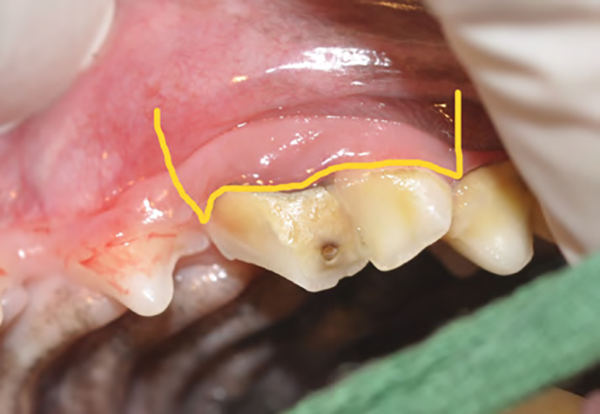

Figure 2A : Illustration (trait jaune) des lignes d’incision gingivale et muqueuse pour l’élévation d’un lambeau mucogingival trapézoïdal lors de l’extraction chirurgicale de la quatrième prémolaire maxillaire (carnassière).